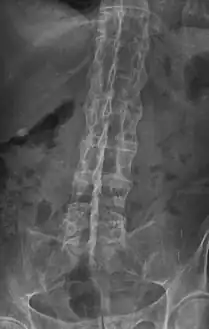

The earliest changes demonstrable by plain x–ray shows erosions and sclerosis in sacroiliac joints. Progression of the erosions leads to widening of the joint space and bony sclerosis. X-ray spine can reveal squaring of vertebrae with bony spur formation called syndesmophyte. This causes the bamboo spine appearance. A drawback of X-ray diagnosis is the signs and symptoms of AS have usually been established as long as 7–10 years prior to X-ray-evident changes occurring on a plain film X-ray, which means a delay of as long as 10 years before adequate therapies can be introduced.[21]

X-ray showing bamboo spine in a person with ankylosing spondylitis -